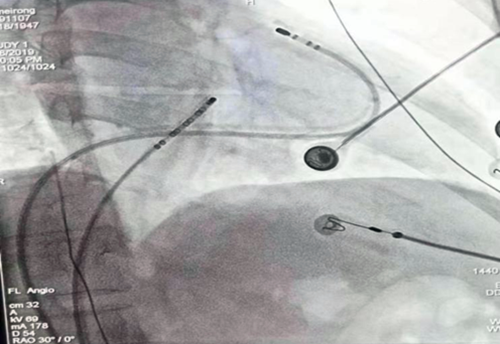

我院心血管二病区副主任医师周勇是这样想的也是这样做的,随着时代变迁、科技发展,心血管疾病的治疗方法日新月异,知识更新很快,科室开展了一系列治疗的新技术、新方法,周勇深知新的领域风险与挑战并存,不学习就要落后,他要求自己不断地钻研业务、精益求精。2018年在院领导的高度重视以及科主任的大力支持下,他创新技术独立完成了房室折返性心动过速、房室结折返性心动过速、典型房扑、室性早搏等快速心律失常的射频消融治疗,手术成功率较高,达到了省内及国内水平,取得了良好的治疗效果,提高了患者满意度。由于技术的不断成熟,目前已经能够独立开展较为复杂的房颤射频消融技术。房颤射频消融术是在X线血管造影机的监测下,穿刺房间隔,把一根直径2.7毫米的细导管经过房间隔送到左心房,沿着左右肺静脉前庭进行环状消融,阻断左右肺静脉与左心房的电传导,对于持续性房颤,还需要进行左房顶部及左房前壁进行线状消融,起到治疗房颤的作用。该项技术要求消融部位精确,消融点与点之间紧密相连,同时手术风险较大,要求术者有一定的技术经验。射频消融治疗房颤较彻底,可以减少症状,可以治疗药物无法控制的房颤,可以避免长期服用抗心律失常药的毒副作用,减少远期脑栓塞的风险。由于该技术对术者要求条件较高,手术复杂,目前在地级市三级医院较少独立开展,该技术的成功开展进一步巩固宿州市立医院心血管内科在我市学科地位。

心律失常是心血管常见病病,发病率较高,尤其是快速心律失常。快速性心律失常包括房速、房扑、房颤、房室折返性心动过速、房室结折返性心动过速、室性心动过速等。经导管射频消融术是治疗快速性心律失常的重要方法及手段。其原理:通过穿刺血管,将电极导管置入心脏心腔内进行电生理检查,明确心律失常的发作机制及维持心动过速的关键部位;再通过电极导管将射频电能引入到心脏的病变处,通过定量释放能量消融病灶达到治疗的目的。与药物治疗相比,射频消融不是暂时性预防或终止心动过速的发作,而是一次性治愈,不再需要使用抗心律失常药物。总之,它是一种安全有效,简便易行的治疗方法。射频导管消融术主要适应症:预激综合征合征、房室折返性心动过速、房室结折返性心动过速、房速、典型房扑、房颤、室早、室速等。